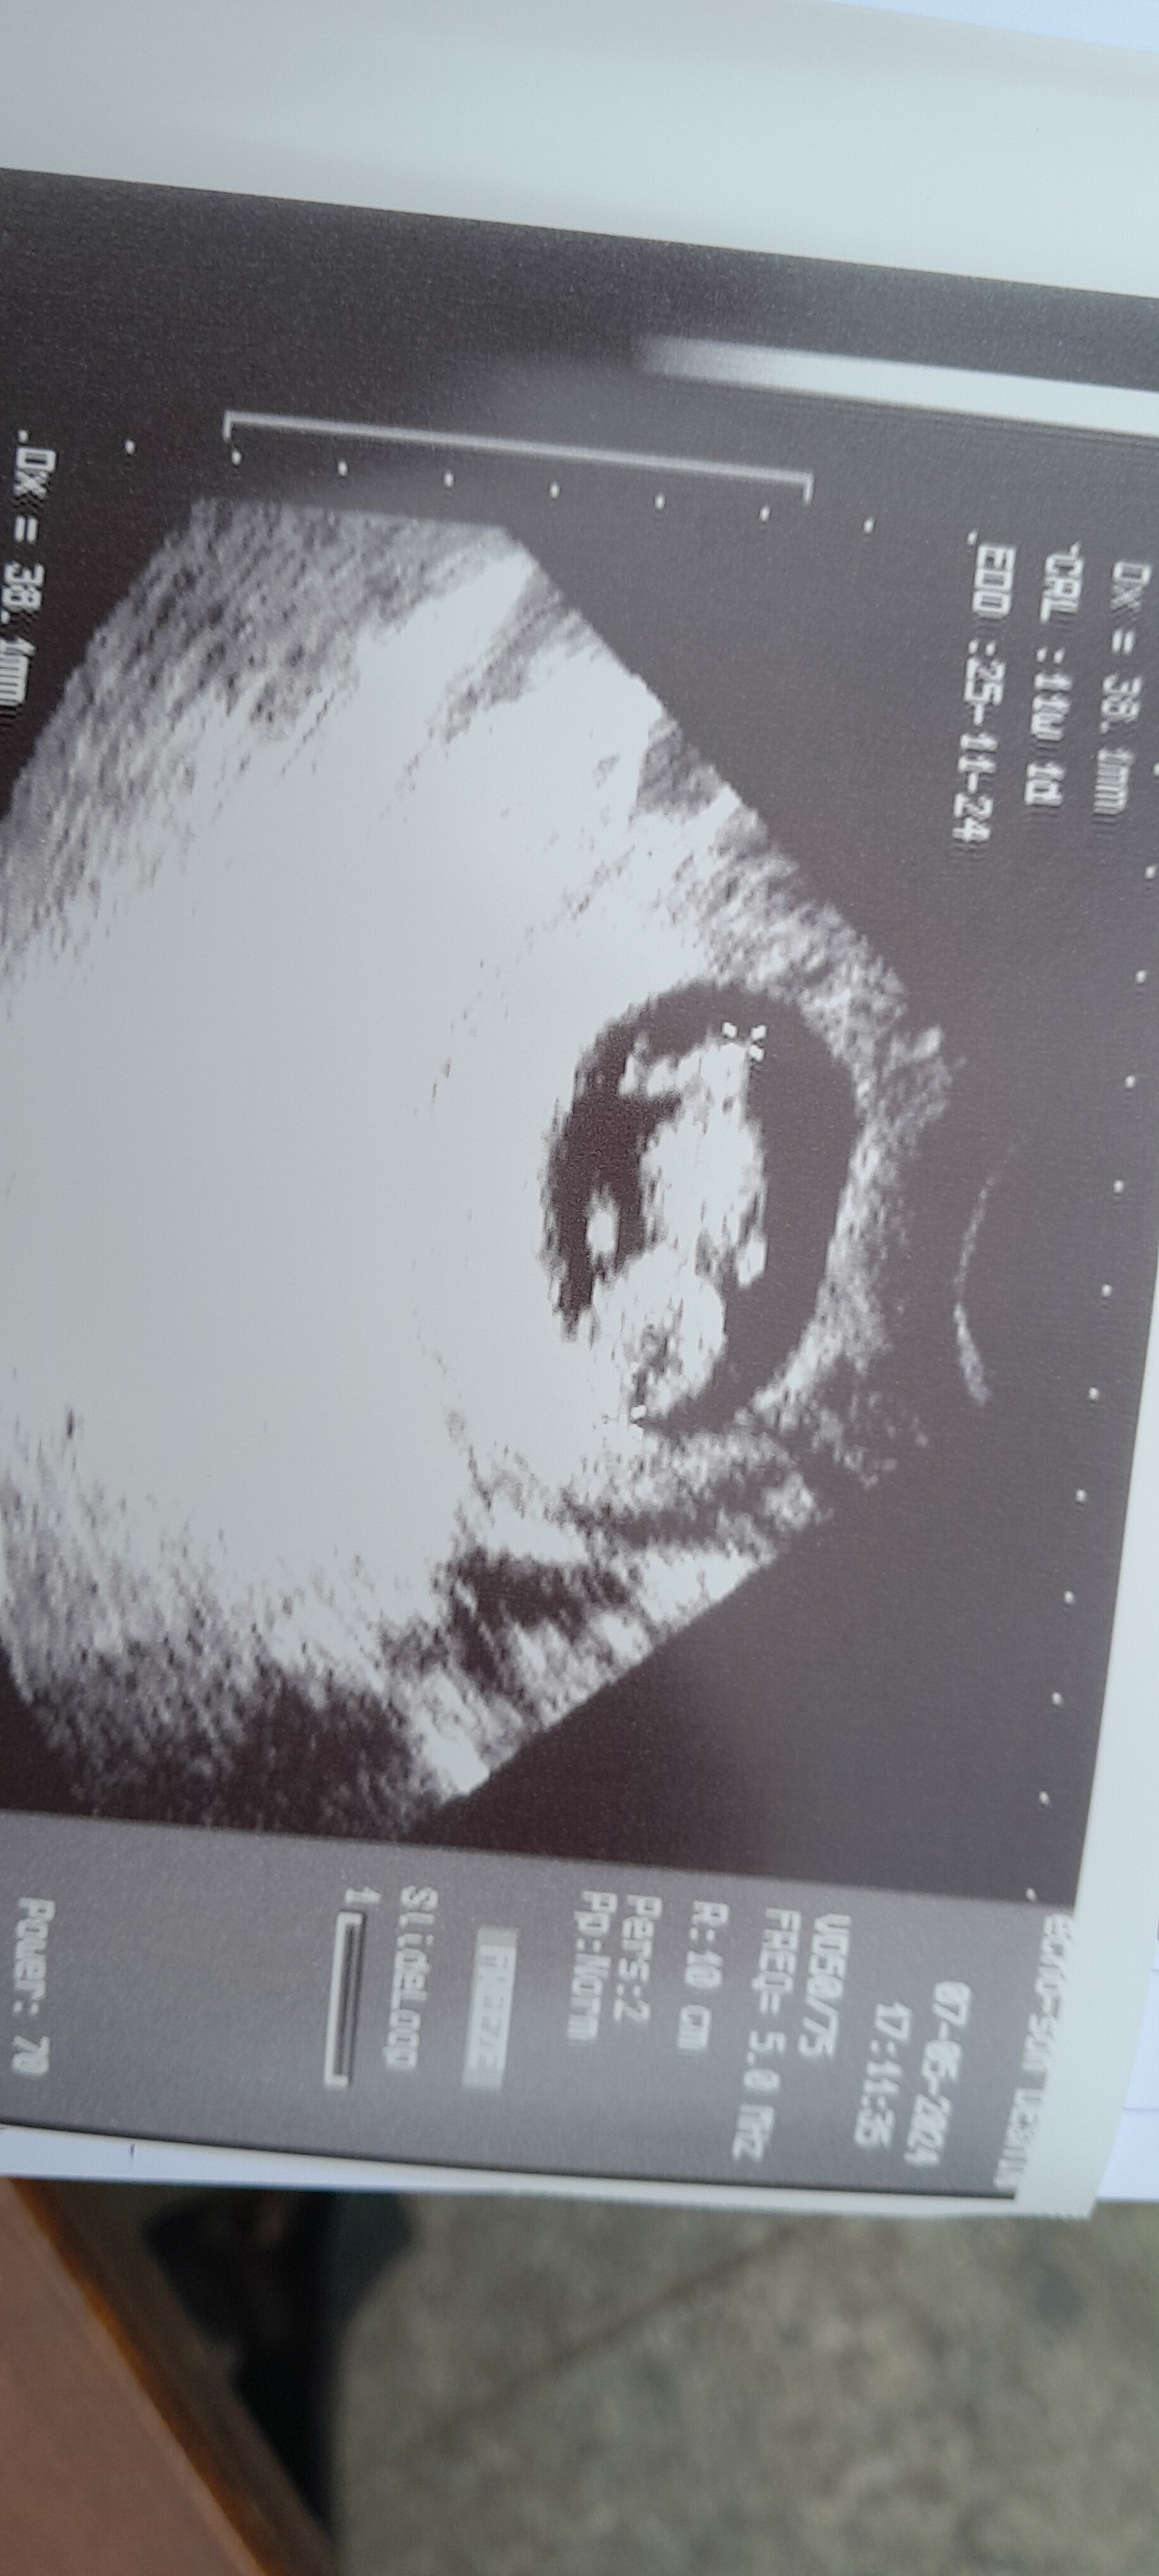

U mnie dzisiaj 10+3, lekarzowi wyszło 11+1, co raczej trochę za dużo, a mlode sie juz wyginalo. Jednak cieszę się, że rośniema prawie 4 cm

termin mi polozna wpisała na 25.11 xd